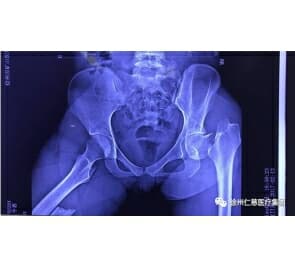

该患者女性36岁,因为车祸导致腰1椎体压缩性骨折,疼痛感剧烈,活动受限。按照以往的常规,这种年龄不足50岁的腰椎压缩性骨折患者只能进行开放性手术修复。但是传统脊柱后路手术存在切口大、肌肉剥离多、出血多、后路稳定结构破坏大、康复慢等不足,这次戴维享主任医师经过认真分析病例后决定创新性引进经皮椎弓根钉内固定的方法。当天下午,戴维享主任医师和王栋主治医师为患者在全麻下进行了经皮椎弓根钉内固定术,在 C形臂透视定位后标记进钉点,腰2、胸12椎体经双侧椎弓根穿刺,抽出针芯,置入导丝,然后,沿导丝置入4枚椎弓根螺钉,置入连接棒,撑开复位,锁定所有固定螺丝。手术时间仅1.5小时,术后该患者腰背部只留下了4个1cm长的点状切口。目前患者恢复顺利,状态良好。